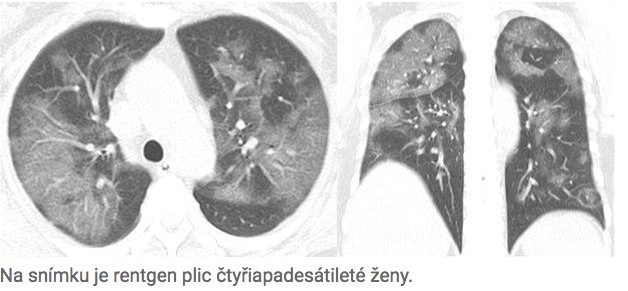

The same phenomenon is observed in other patients as well. For example, this X-ray belongs to a 54-year-old woman who, after returning from the Chinese epicenter of the outbreak in Wuhan, suffered fever, a severe cough, fatigue, and chest tightness.

The white spots on the X-ray also increase on the lungs as the disease progresses. The condition of untreated patients therefore deteriorates significantly.